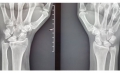

extensor tendon synovitis [ Dorsal Middle Soft Tissue Pain ]

extensor tendon synovitis